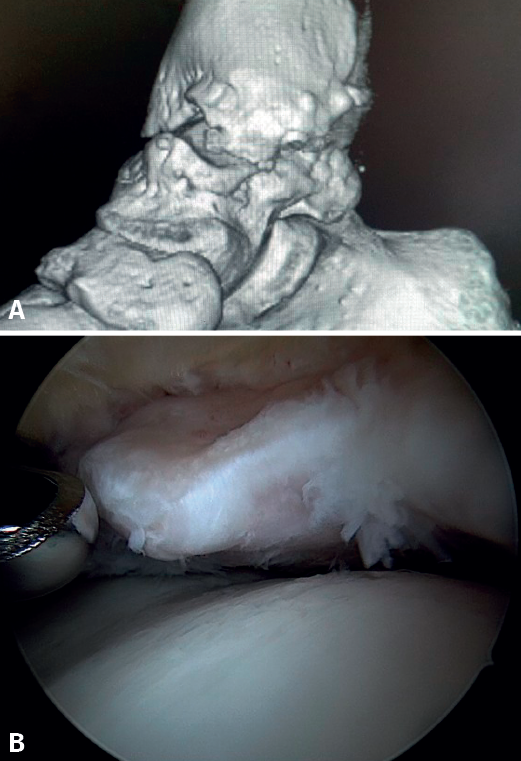

El PAT óseo por osteofitos también ha sido relacionado con la presencia de inestabilidad crónica. Se ha postulado que la alteración en la cinemática articular secundaria a la insuficiencia ligamentosa favorece el desarrollo de osteofitos en la región anterior de la tibia y el astrágalo(36,37). Estudios recientes han cuestionado la teoría de tracción capsular repetida como origen de los osteofitos en la práctica deportiva(38), ya que es fácilmente demostrable que los osteofitos se localizan intraarticulares por dentro de la inserción capsular, en el contexto de una artroscopia de tobillo (Figura 2). Por ello, la artroscopia con dorsiflexión de tobillo es fundamental para poder resecar los osteofitos de forma segura sin daño capsular ni a las estructuras suprayacentes, mientras que la técnica clásica de tracción (invasiva o no) dificultaría enormemente su resección, por lo que hoy en día se desaconseja su uso rutinario(3,39). Vega distingue dos tipos de osteofitos(3), según sean por trauma repetitivo (forma de pico) o por inestabilidad (en forma de visera). El concepto de microinestabilidad se asocia a microtraumatismos de repetición que podrían ser el origen de osteofitos con esta morfología característica (Figura 3).

Figura 2. Osteofito anterior de la tibia. A: en dorsiflexión la cápsula se separa del osteofito permitiendo su resección (B) mediante fresado.

Figura 3. Osteofito por inestabilidad crónica. A: el osteofito conforma un tope óseo que se extiende en el borde anterior del plafón tibial y la cara anterior del maléolo medial; B: imagen artroscópica.